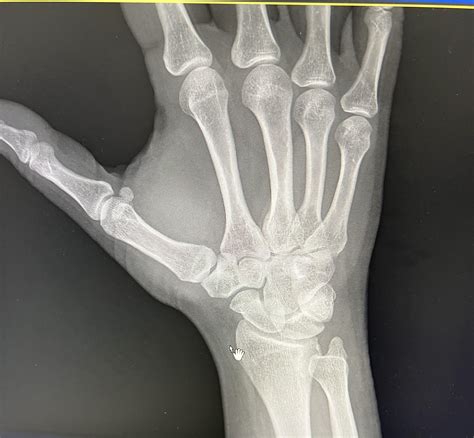

Because hairline fractures are so subtle, they are notoriously difficult to see on standard X-rays, especially in the first few days after an injury. Medical professionals often utilize a combination of clinical physical exams and advanced imaging to confirm the diagnosis.

Standard X-Ray Initial screening to rule out complete breaks or dislocations.

MRI or CT Scan Used when X-rays are inconclusive to identify microscopic cracks.